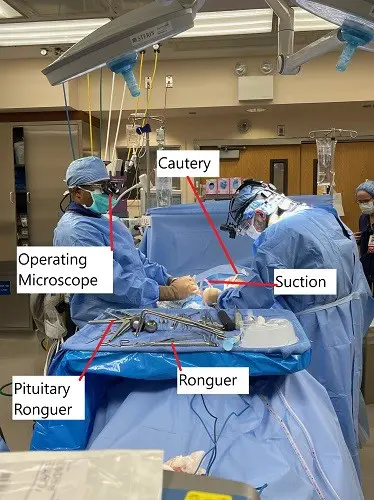

- Microdiscectomy: A minimally invasive procedure that removes the herniated part of the disc, relieving pressure on the nerve roots. Typically used for single-level disc herniations.

- Microdiscectomy:

- Recurrent Herniation: A small risk of the disc herniating again at the same level.

- Nerve Injury: Though rare, there is a small risk of damaging the spinal nerves.

- Infection: Though uncommon, there is a risk of infection at the incision site.